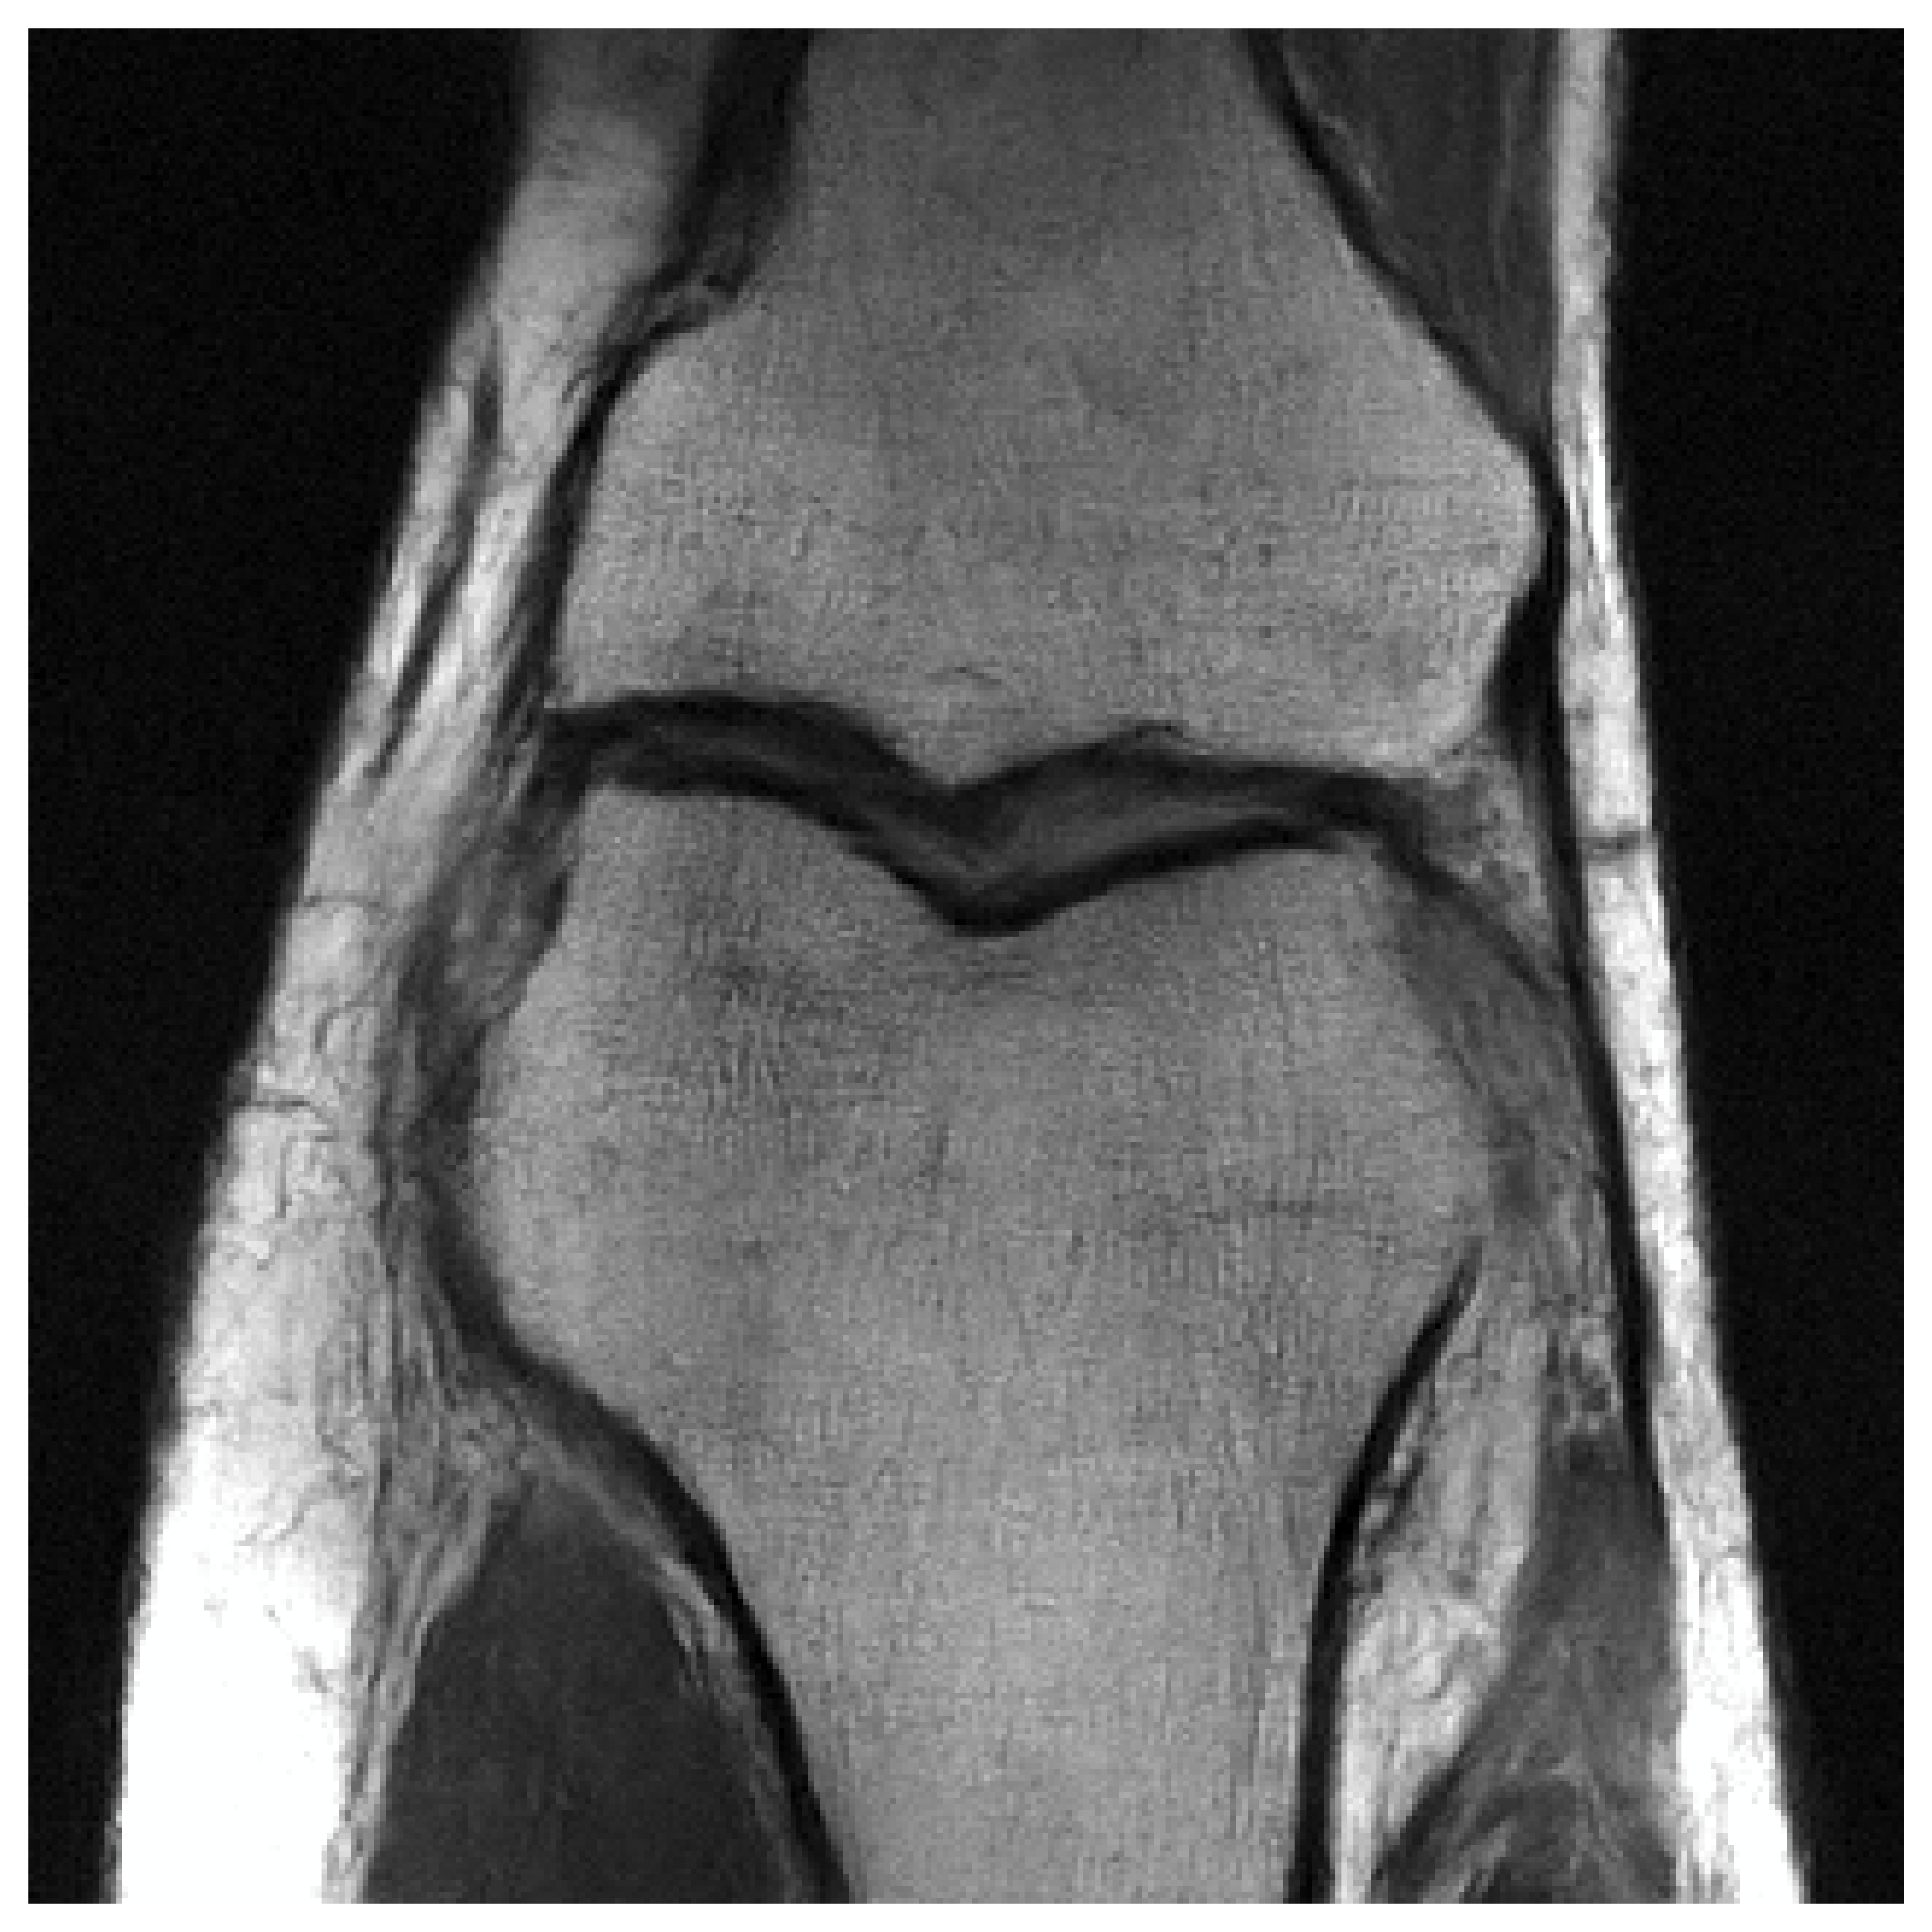

and optimal experimental design for accelerated Magnetic Resonance Imaging

“Probabilistic Bayesian optimal experimental design using conditional normalizing flows”